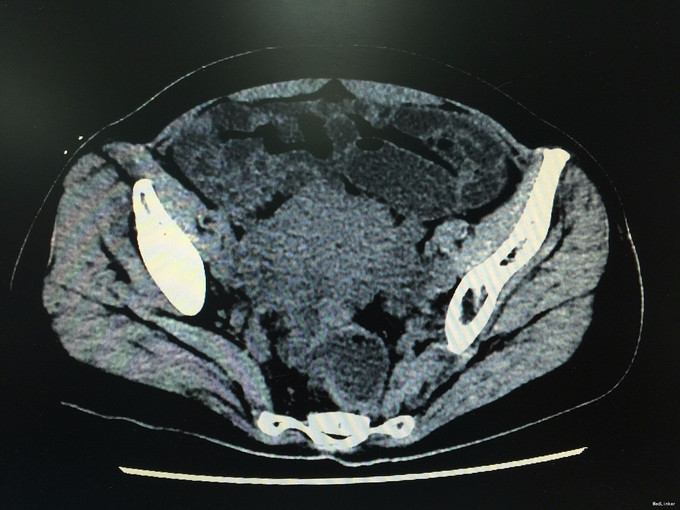

查体无特殊。辅助检查:全腹螺旋CT平扫+增强:1.考虑结肠癌,侵及肠壁全层,并盆腔、子宫直肠陷窝多发种植转移,子宫受侵,双侧附件转移,腹膜及大网膜广泛种植转移。2.肝多发转移瘤:脾门区多发结节,转移瘤可能性大。3.肝左外叶异常灌注。4.胆囊泥沙样结石,慢性胆囊炎。肠镜提示:1.直肠粘膜下隆起(囊肿?)2.内痔。进一步行肝穿刺:病理符合中分化腺癌,免疫组化提示肠癌转移可能性大。

诊断:转移性腺癌:肠癌? 排除化疗禁忌症予FOLFOX方案化疗3程。疗效评估PD。